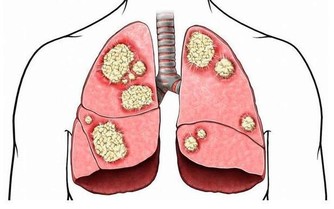

隨著我國進入老齡化社會,腎病患者也以驚人的速度逐年上升,發病率已高達10.8%。

在我國,慢性腎病患者已多達1.3億人,即大約每10名成年人中,就有1人存在某種形式、不同程度的腎臟受損。

腎臟好比人體的污水淨化站,擔負著過濾、消除有害物質的功能,同時保護對生命活動有重要作用的蛋白質、水分和鹽類不致流失,保持人體水液平衡。

因此,腎臟一旦發生故障,就不能消除各種有害物質和多餘水分,還會導致大量營養物質流失,引起水液代謝失調、酸鹼平衡失調等現象,嚴重時甚至危及生命。